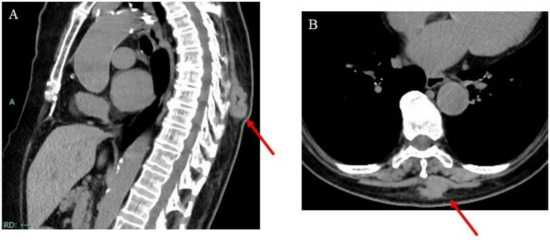

2. Case Presentation